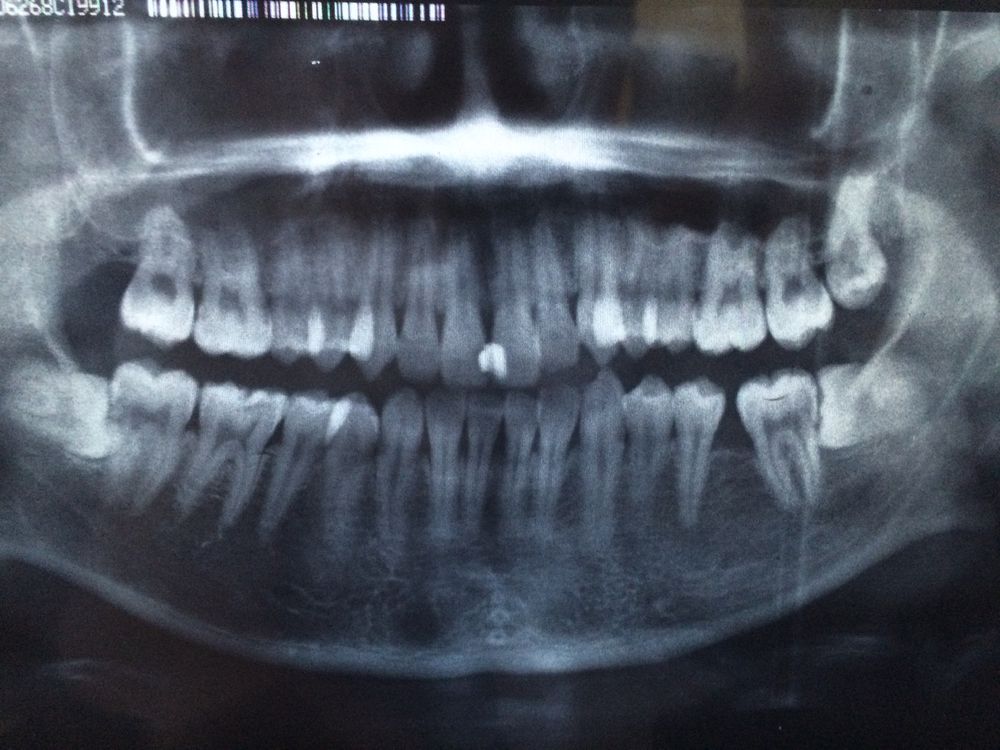

1.门牙2个都要做根管.我已经开始做了.左门牙上面有个囊肿.右门牙也有点鼓.不过很少...大夫说先做根管..治疗看看....

2.右上智齿已经是龋齿,做根管时候拔出了..

3.右下阻生齿已经把牙顶歪了.那里本来就拔了个牙.是否可以先放弃拔出...

4.左下阻生齿想处理,得有多麻烦..!?

左右说反了,片子应该反着看。处理没问题。下面两个智齿都该拔,右下智齿优先拔。片子不清楚,但我感觉七的牙根是不是断了

:根管治疗消不了囊肿,要考虑手术切除。七就是智齿前面那颗牙。拔牙打麻醉,当时是不会很疼的